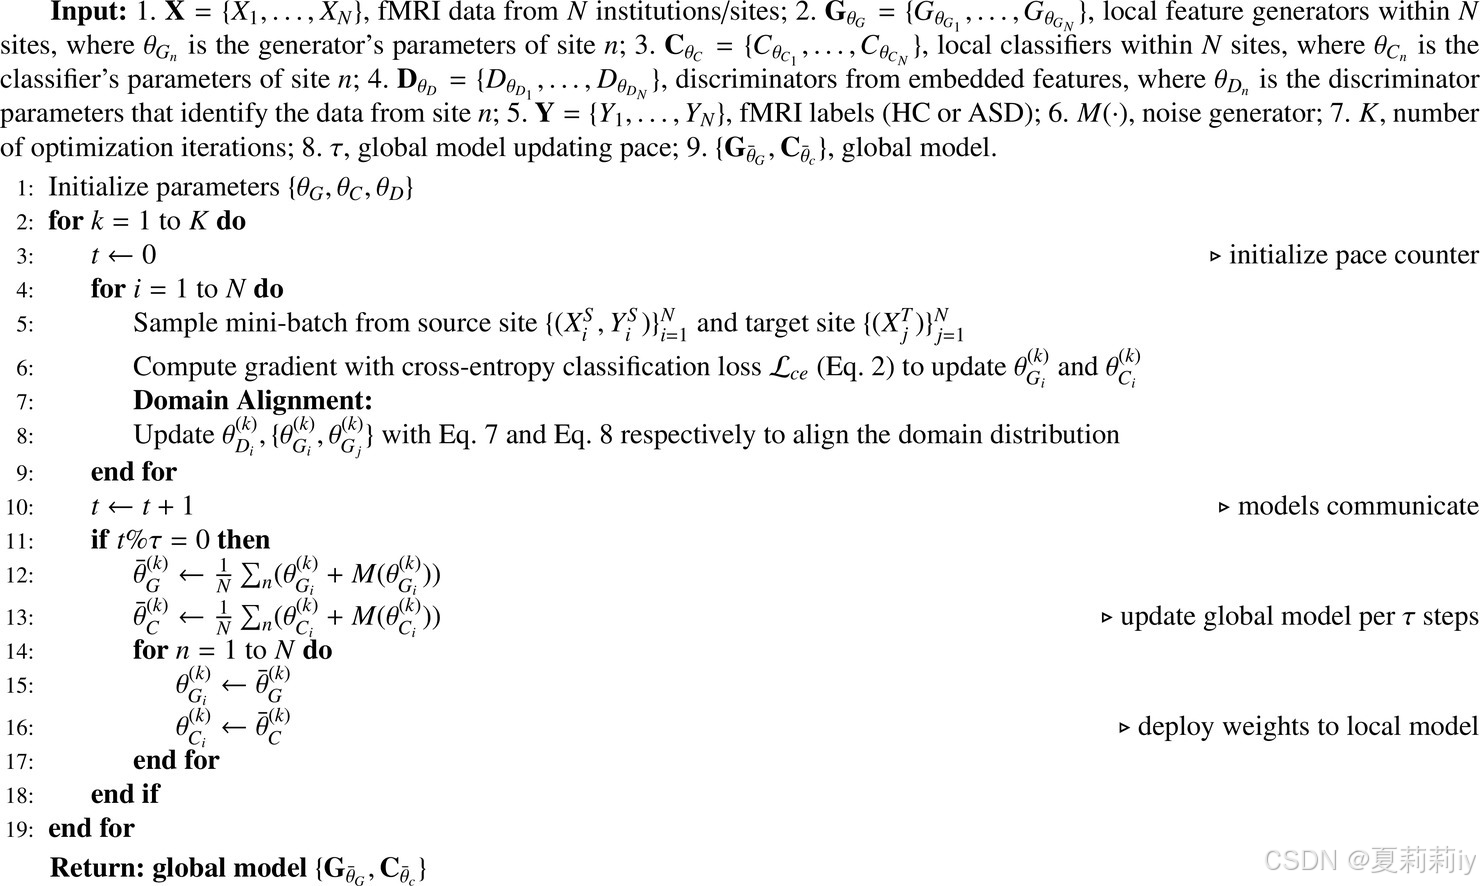

⑦Algorithm(在这个第八行感觉出⑤和⑥俩损失就是直接都用上就行,但是作者也没有特别的解释,不知道从哪扒来的):

(1)Participants

①Sites chosen: the largest four, UM1、NYU、USM、UCLA1 with 106, 175, 72, 71. Eliminating incomplete data samples, left 88, 167, 52, 63 each

②Atlas: HO with 111 ROIs

③Slicing window: 32 size with 1 stride to crop the original time series

④Sample statistics:

⑤Demographic data: